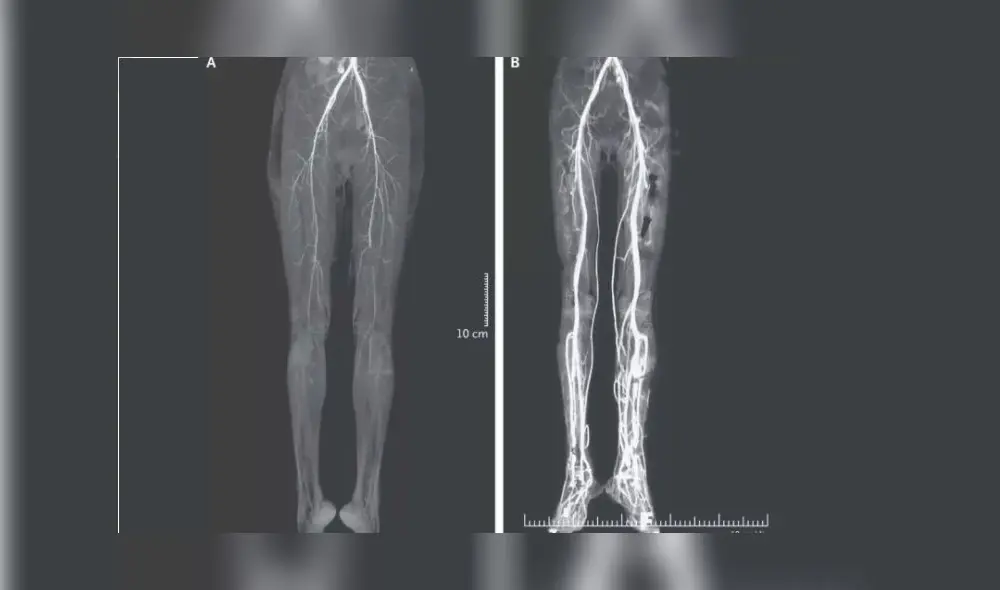

A la paciente de este caso le practicaron una tomografía computarizada, la cual reveló que sus se habían estrechado y, por lo tanto, habían reducido el flujo sanguíneo hacia sus piernas, por eso estaban “descoloridas”.

De todos modos, una tomografía computarizada (TC) dos semanas después mostró un mejor flujo sanguíneo en ambas extremidades.